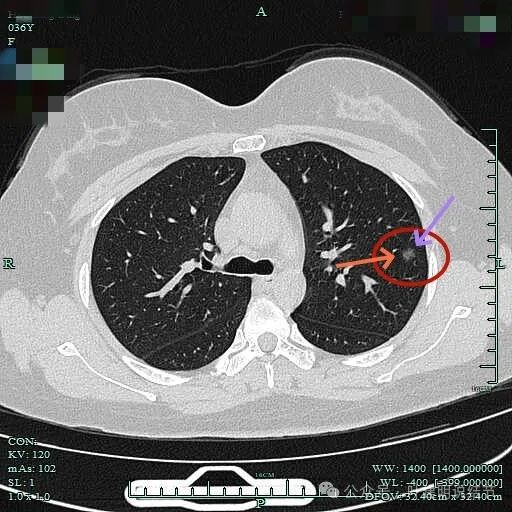

病灶小却边缘毛糙有毛刺,也见血管穿行的样子,表面不平,整体轮廓清。